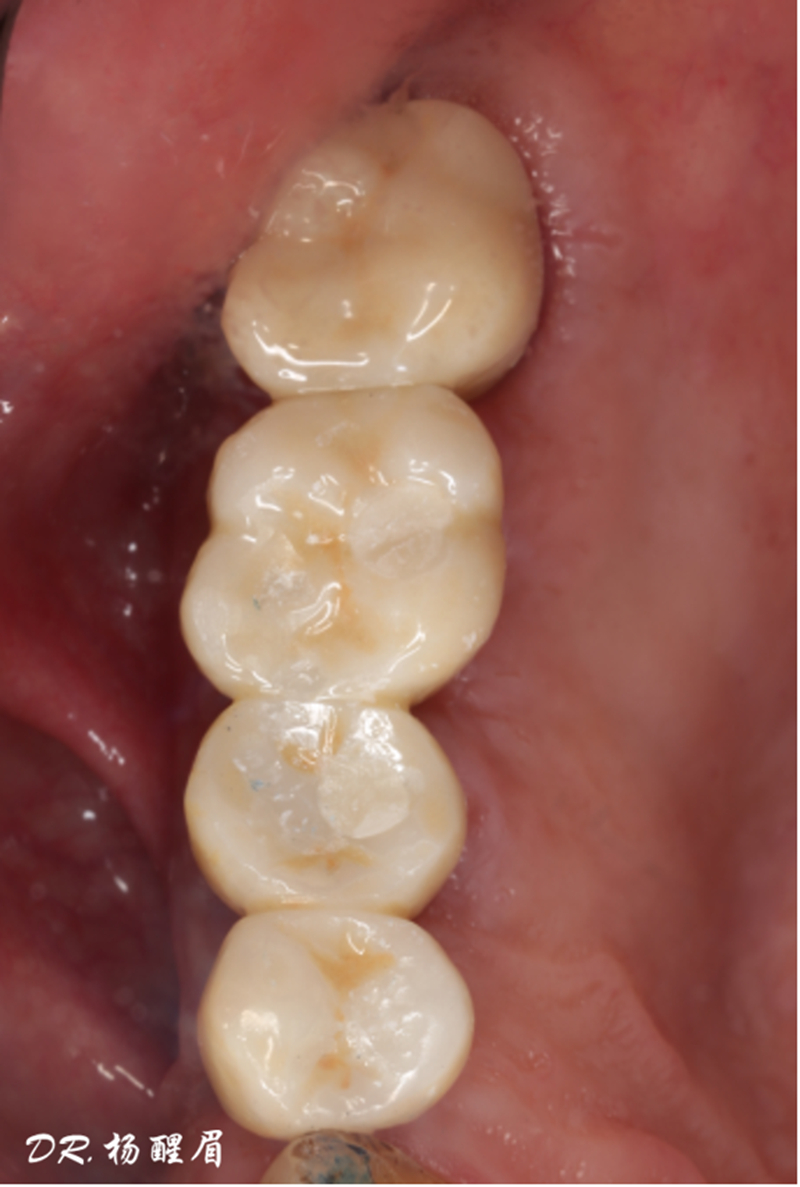

修復完成